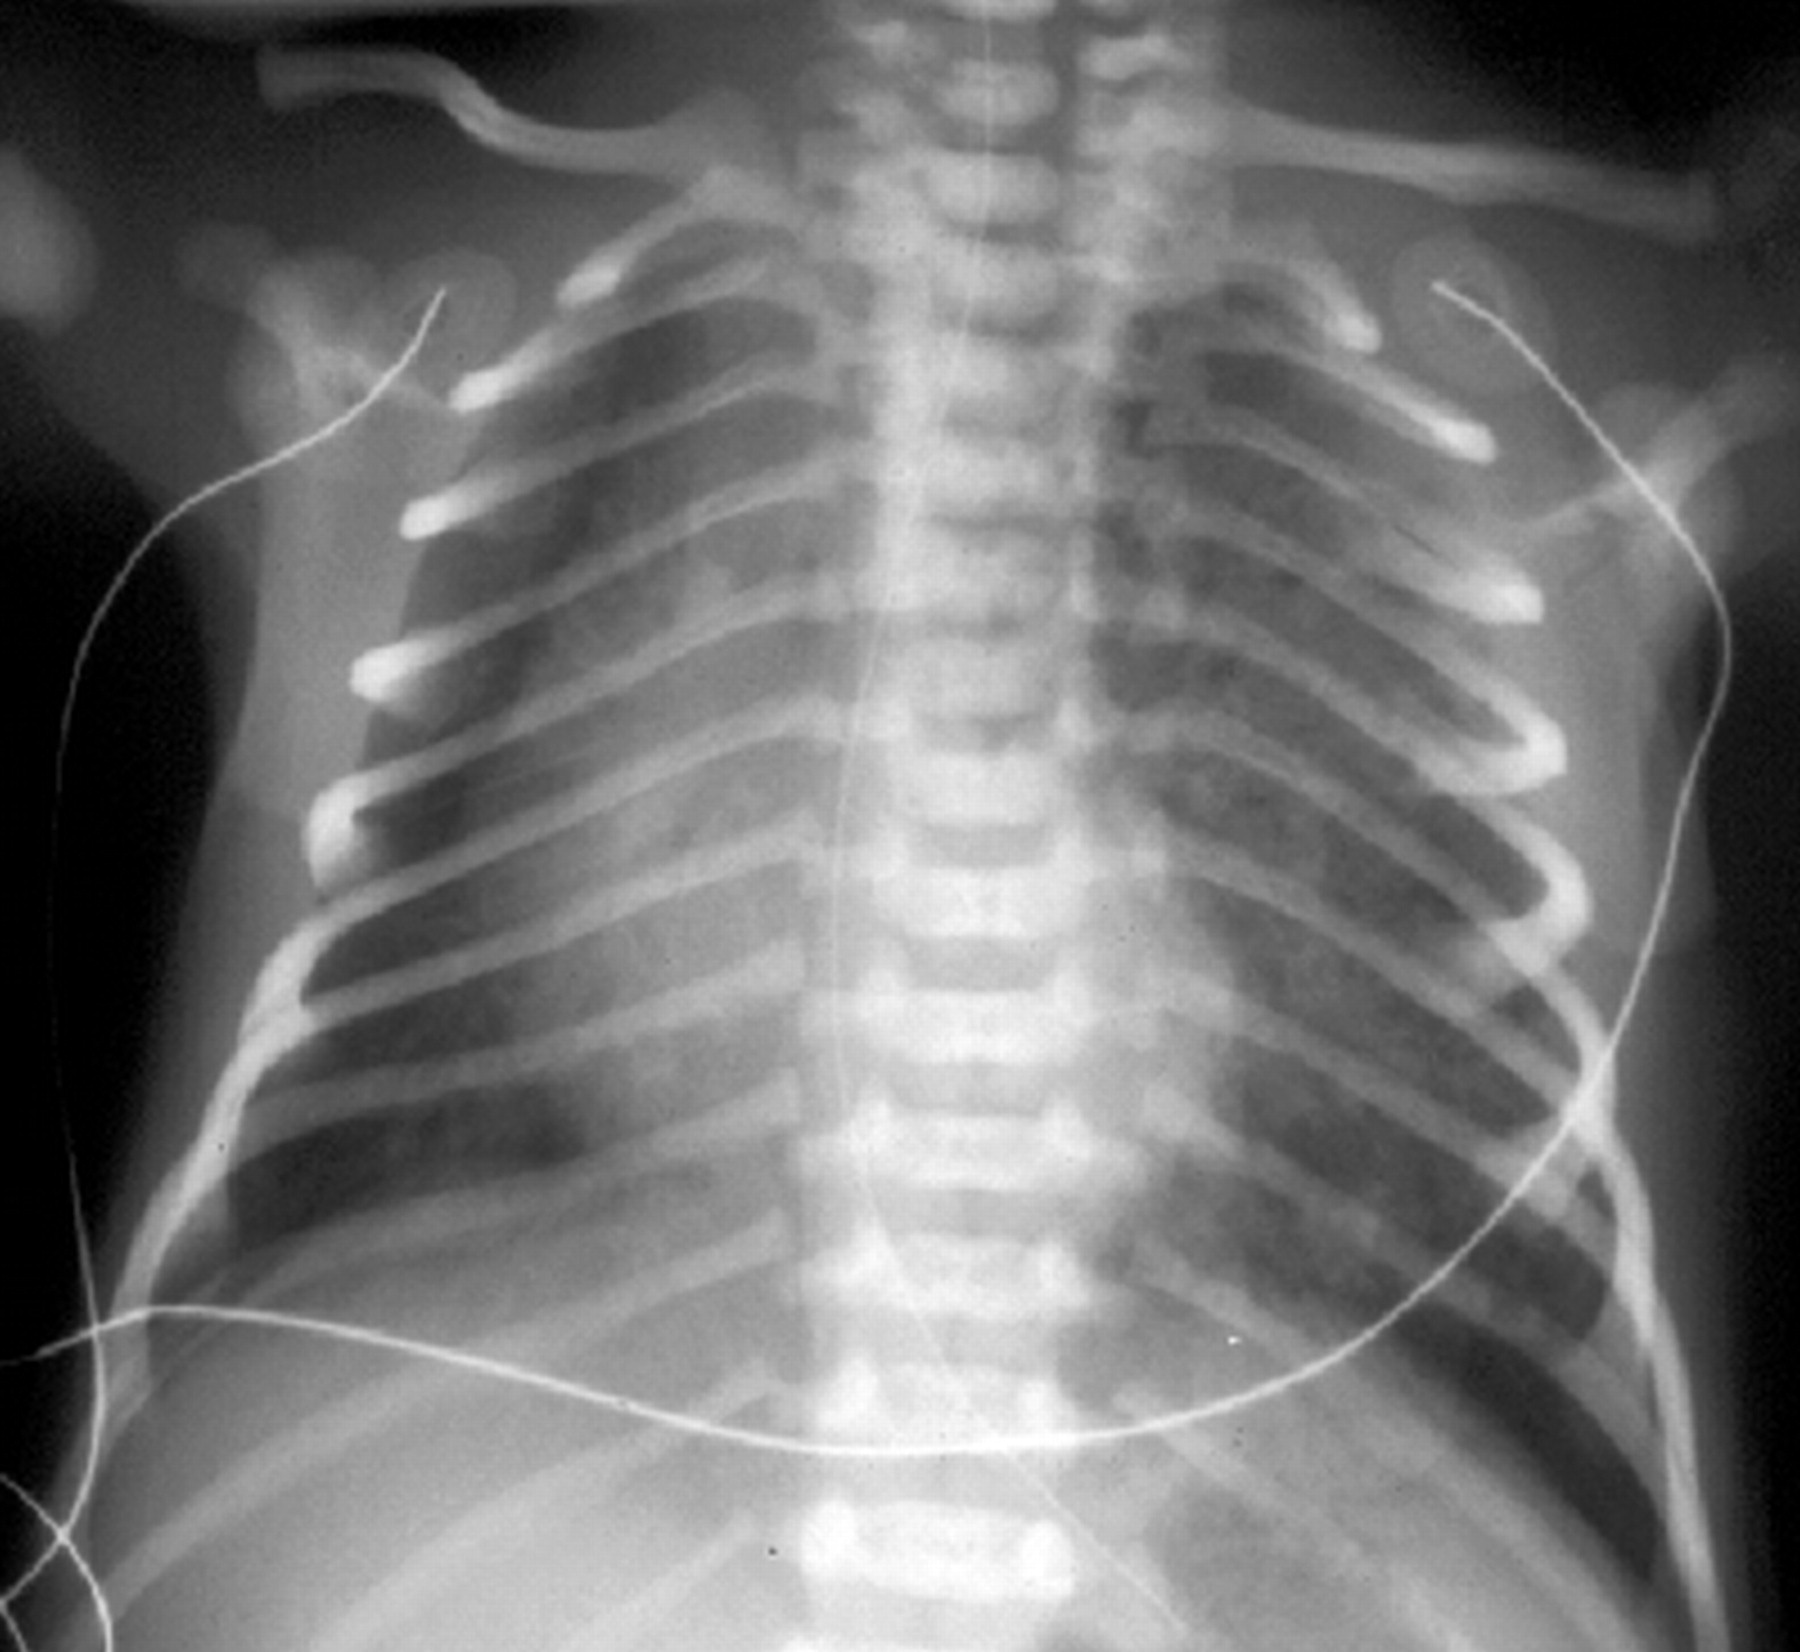

Рентгеновские снимки при врожденной эмфиземе легкого

Раздел: Визуальные уроки